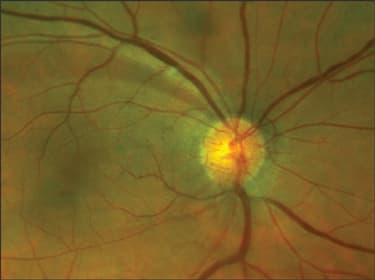

Physicians also use ultra-widefield imaging to more accurately diagnose and manage glaucoma. Doctors can get a clear view of the optic nerve, measure it and examine it in both eyes side by side. In addition, clinicians can measure the ISNT rule and examine the remaining fundus to determine if any retinal pathology exists well into the periphery that might be affecting the optic nerve. These views help confirm whether or not a patient is a glaucoma suspect. "Our technology enables you to pinpoint glaucoma indicators, such as defects in the superior arcade and breaks in the retinal nerve fiber layer, which are linked to an early indication of glaucoma risk," Mr. Anderson says. "Looking at the optic discs on screen side by side is the fastest way to find asymmetry, which is one of the biggest risk factors in determining a glaucoma suspect. You can zoom in on the discs so they take up 90% of the screen."

According to Dr. Neatrour, ultra-widefield imaging enables him to see the optic nerve more clearly and document damage that occurs over time due to glaucoma progression (Figure 4).

Figure 4. With ultra-widefield imaging, physicians can pinpoint glaucoma indicators, such as defects in the retinal nerve fiber layer (shown here), which are linked to an early indication of glaucoma risk. They can view optic discs on screen side by side to find asymmetries — one of the biggest risk factors in determining a glaucoma suspect.